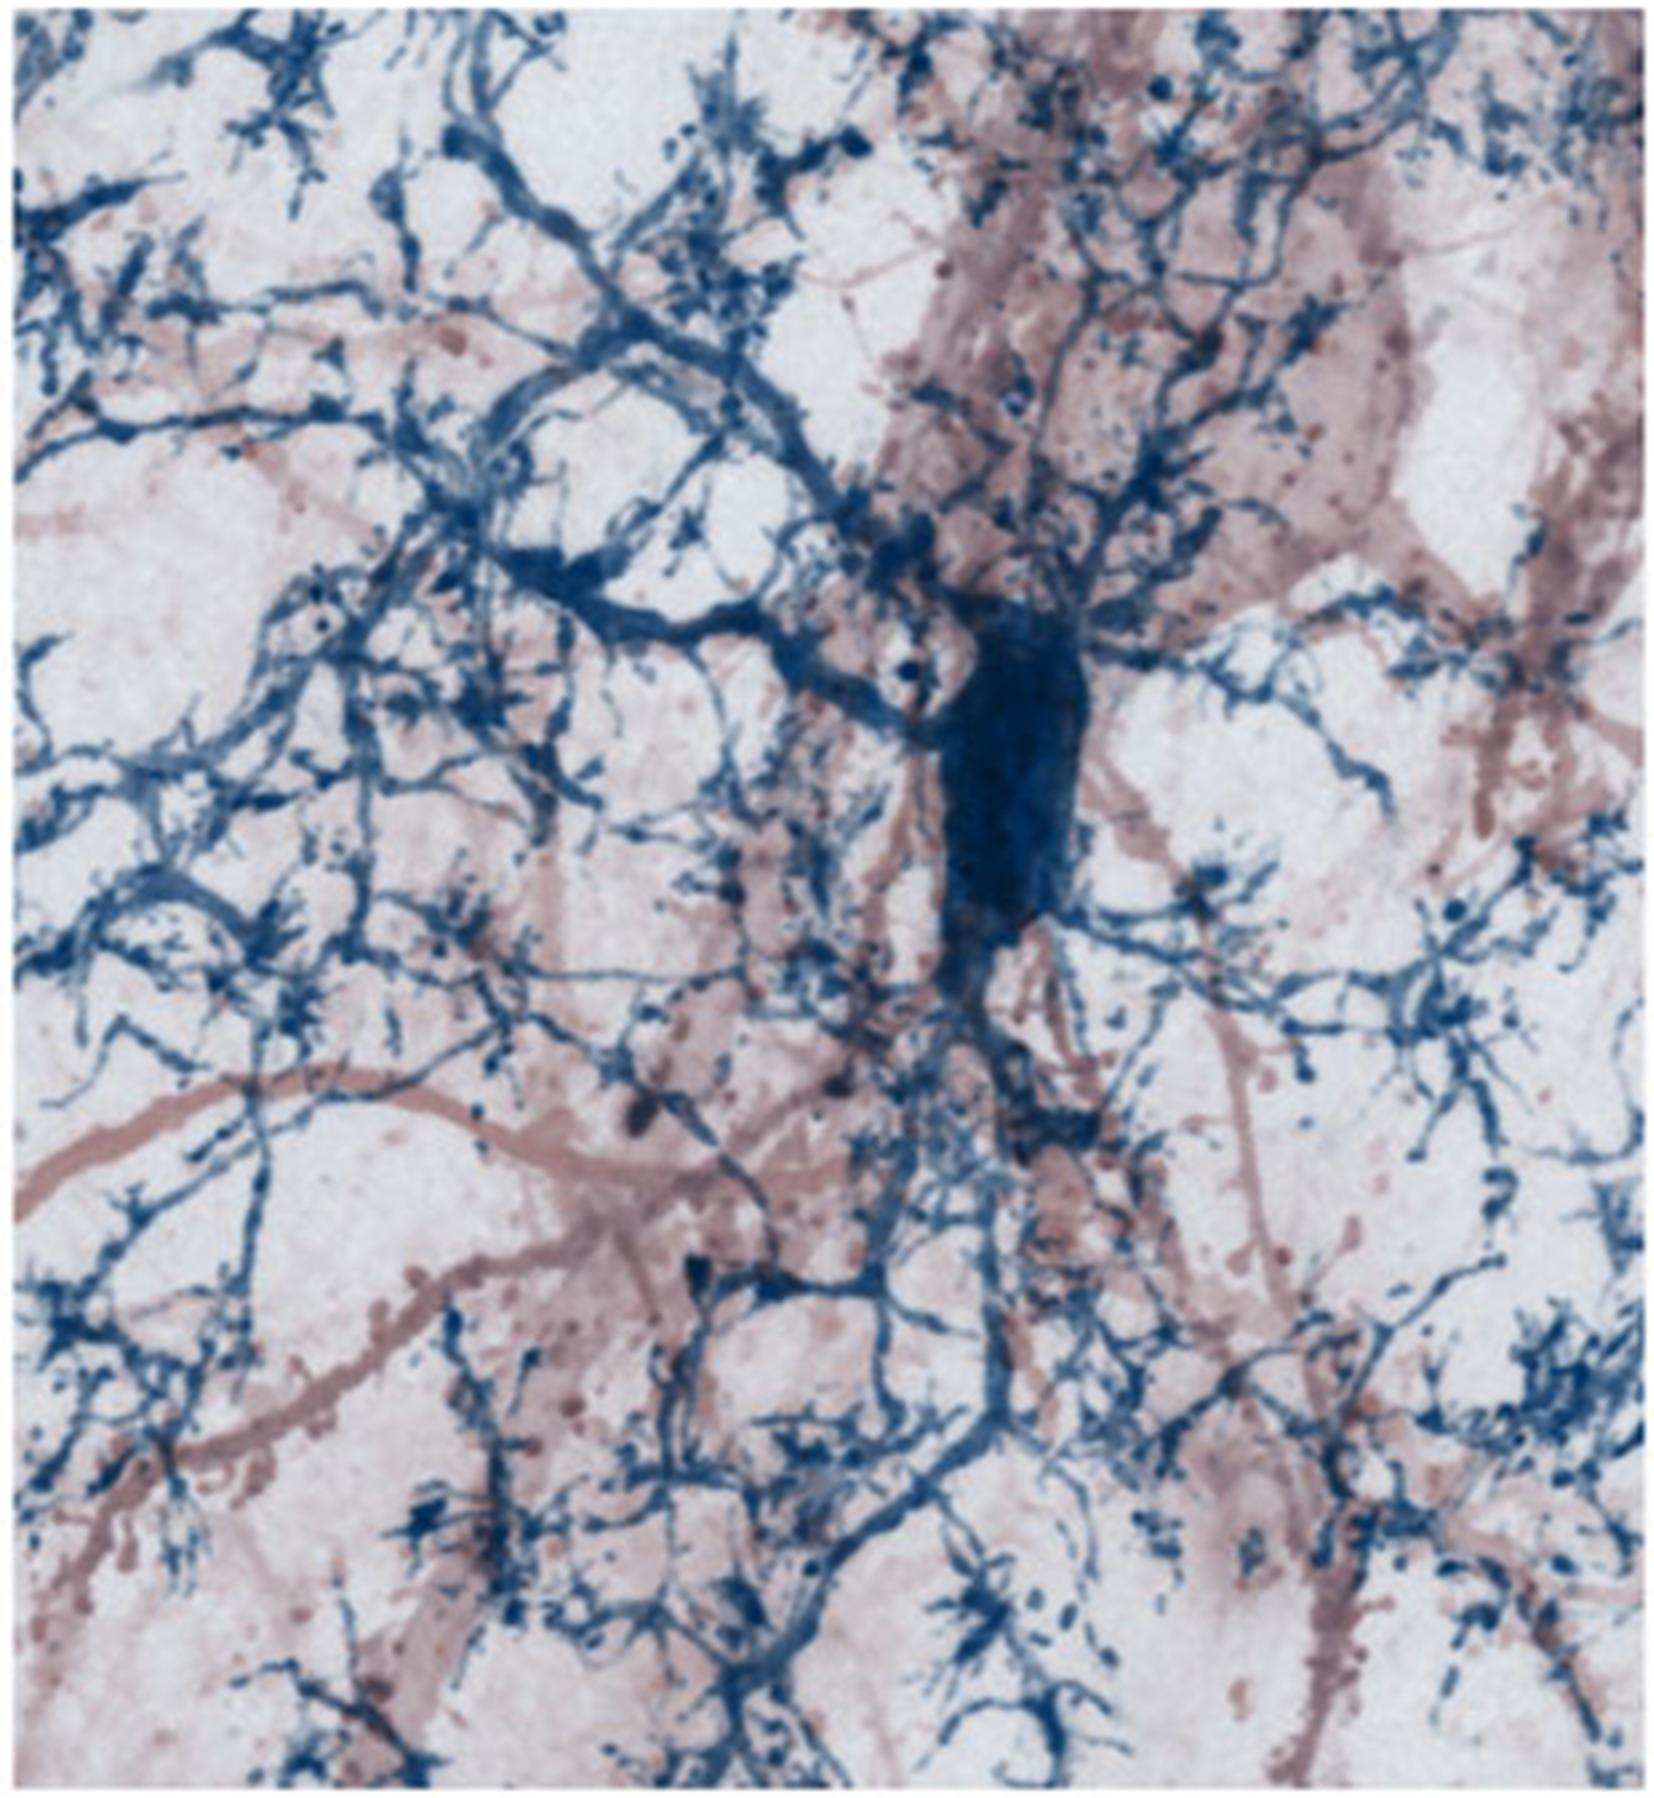

Loss of synapses – the structures that serve as functional contacts between nerve cells – is an early indicator of damage to the cerebral cortex in cases of progressive MS. The researchers therefore suspected that the synapses are the key to the neuronal damage that ensues in this stage of the disease. With the aid of various imaging techniques, the team was able to demonstrate that such widespread loss of synapses can be reproduced in a mouse model of MS. Moreover, their observations revealed that synaptic spines are destroyed by a specific type of immune cells. “These immune cells preferentially eliminate spines, which contain high levels of calcium. We assume that the inflammation reaction itself triggers an influx of calcium, which destabilizes the spines,” says Kerschensteiner. “These changes in late-stage MS are reminiscent of those that can also be observed during the early phases of neurodegeneration,” Misgeld adds.

The activated immune cells primarily attack excitatory synapses, which are responsible for activating other nerve cells. As a consequence, the level of activity in neural networks decreases. “The nerve cells are effectively silenced,” says Kerschensteiner. “However, much to our surprise, we discovered that this process is reversible in our model.”